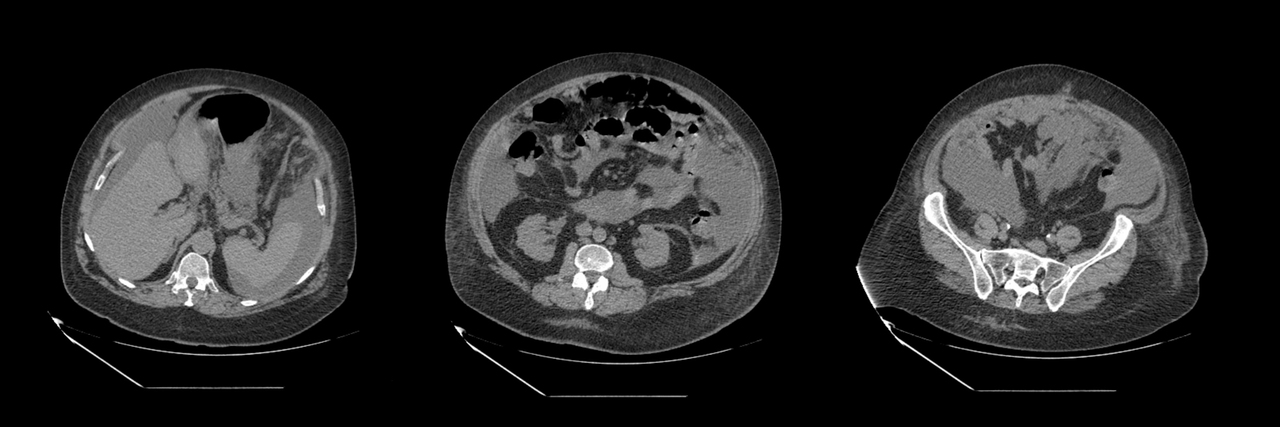

Images clés du scanner :

Question 12 : Vos examens permettent de conclure :

Carcinose péritonéale connue, présence d’ascite au scanner, pas d’autre cause d’occlusion évidente et ascension du CA 125 est faveur d’une progression tumorale

Progression biologique devant une augmentation du marqueur tumoral significative (au moins 30 %)